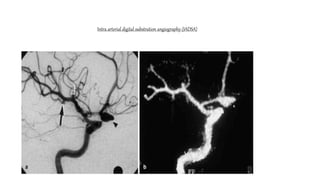

Intra arterial digital substration angiography (IADSA)

Most sensitive tool for the detection of intracranial

aneurysm and should be performed with in 24 hours from

bleeding

Used to demonstrate the aneurysm ,its neck ,size,

location, associated cortical branches, vasospasm, and

additional aneurysm

Performed with selective injection of ICA and vertebral

arteries in order to investigate entire cerebral vasculature

Intra arterial digitalsubstration angiography (IADSA) Most sensitive tool for the detection of intracranial aneurysm and should be performed with in 24 hours from bleeding Used to demonstrate the aneurysm ,its neck ,size, location, associated cortical branches, vasospasm, and additional aneurysm Performed with selective injection of ICA and vertebral arteries in order to investigate entire cerebral vasculature

Intra arterial digitalsubstration angiography (IADSA)